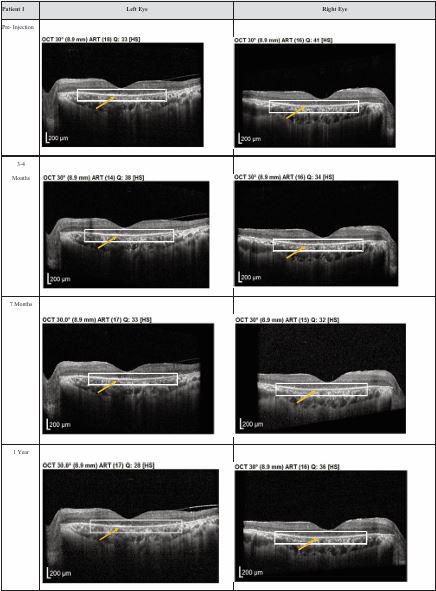

Both patients received a total of seven mesenchymal stem cell (MSC) transplantations, administered every 4-6 weeks, with follow-up from November 2020 to November 2022. Both patients reported no deterioration in vision since the first subtenon implantation in November 2020. Optical coherence tomography (OCT) images consistently demonstrated the maintenance of a hyperreflective region, with no notable increase in intensity. The previously reported improvements in visual function remained stable throughout the two-year follow-up, with no evidence of regression (Figures 1,2).

Figure 2 Optical coherence tomography (OCT) images for both eyes of Patient 2 from pre-injection up to 11 month follow- up. Orange arrow demonstrates the presence of hyperreflective material at the interdigitation area of the photoreceptors at the macula and extramacular region. These were observed and maintained until the last follow-up examination.